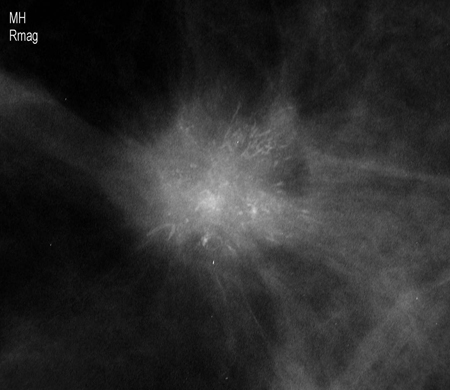

Visualização de magnificação demonstrando uma massa espiculada irregular com calcificações associadas

Cortesia da Dra. Nancy Pile, Universidade de Louisville; usado com permissão